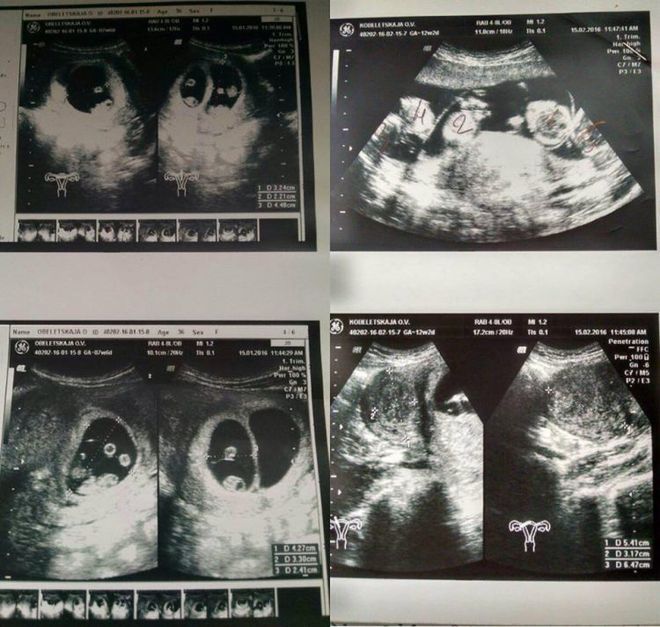

Итак, по итогу по результатам УЗИ выяснилось, что Оксана ждет пятерняшек! Такой редкий случай, когда без искусственного оплодотворения происходит такое чудо! Статистика говорит о случайности такого явления 1 к 55 миллионам! Пока Оксана переваривала эту новость, по больнице быстро пронеслась молва об уникальной пациентке, такого в их практике не было, и, думаем, не будет за всю их жизнь!

«Все было как у всех: голый живот, гель и датчик.

Но когда доктор начала смотреть в экран, у нее сильно изменилось лицо, и я не на шутку испугалась,» — вспоминает Оксана. — «Помню как она начала вслух считать количество плодов и приговаривала, что за такое мне должны подарить дом у моря…